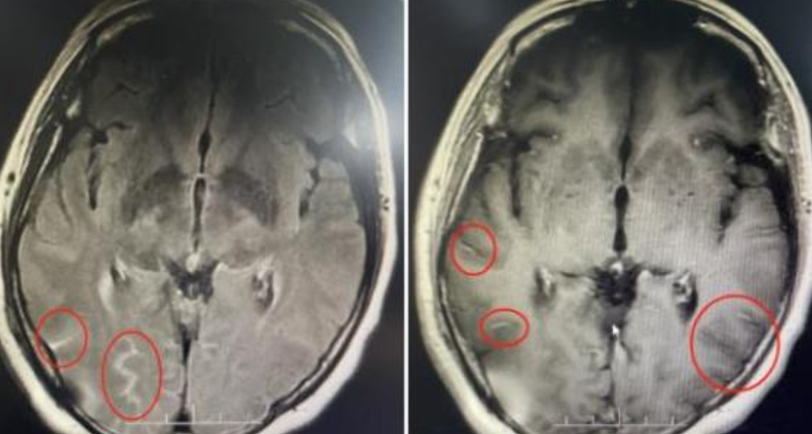

梅姨近期發燒感冒後出現持續頭痛,看醫生後被認為是頸椎病引發,然而劇烈的頭痛讓她每天服用六顆止痛藥仍無法緩解,「痛得腦袋像要炸開,整個人快痛得要『沒了』一樣」。在經過了10天煎熬後,她前往廣東三九腦科醫院就診,經檢查發現頭痛並非由頸椎病引起,而是由隱球菌腦膜炎所致。這種由真菌引起的疾病主要影響中樞神經系統,死亡率相對較高。醫生指出,梅姨的顱內壓增高,對腦組織造成了壓迫,並引起了一系列神經損傷,包括視力和聽力的下降。在接受抗真菌治療後,梅姨情況仍然嚴重,左眼視力更幾乎喪失。隨後醫生緊急進行手術,頭痛最終得以緩解,視力也恢復正常。